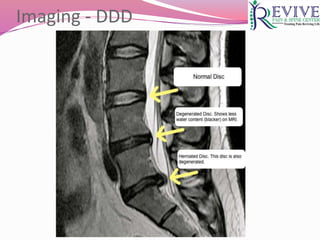

 Syn : Discogenic pain, internal disk disruption (IDD),

degenerative disk disorder (DDD)

 It is a physiologic consequence of aging

 Black disc disease on MRI  dessicated discs (loss of

signal on T2 weighted images)

 Presence of HIZ in posterior annulus on T2

Imaging - DDD

HIZ